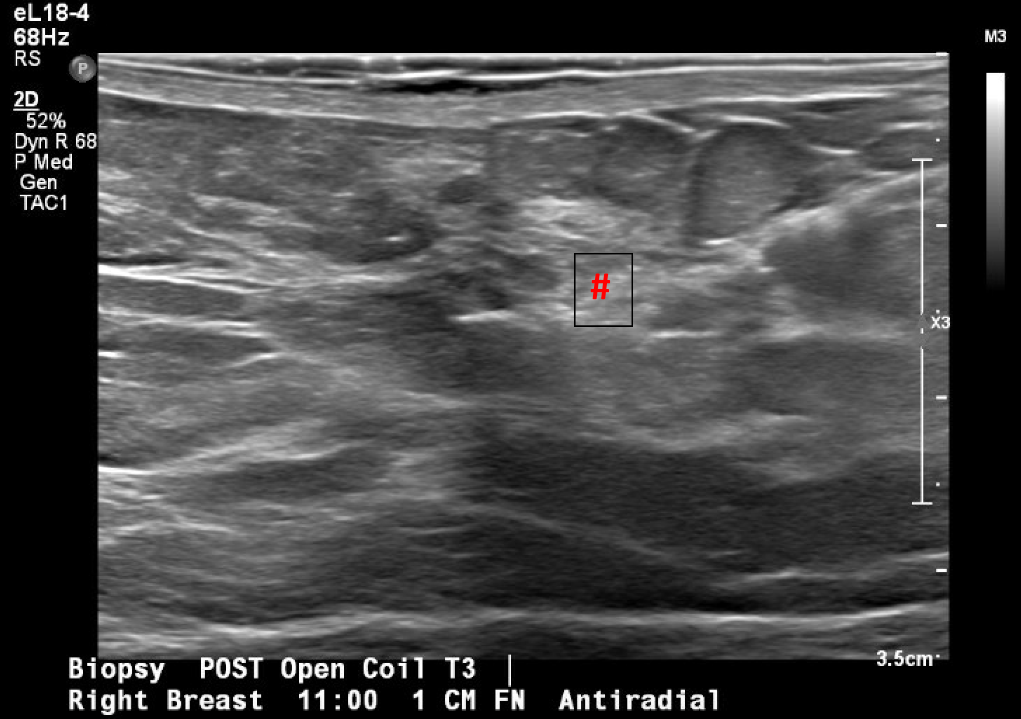

Se trata de una mujer premenopáusica de 46 años, sin antecedentes médicos o quirúrgicos, que acudió inicialmente a la clínica de cirugía mamaria después de que su mamografía anual de cribado descubriera una masa mamaria derecha no palpable de 0,6 x 0,8 x 0,7 cm a las 11 horas (oc), a 1 cm del pezón (FTN) (Figura 1). Se sometió a tres mamografías de detección previas sin ningún hallazgo notable. La mamografía de tamizaje se declaró no concluyente (BI-RADS 0) y se completó una ecografía mamaria con hallazgos similares. Una conversación más detallada con la paciente reveló que se había observado una secreción sanguinolenta en el lado derecho de su sostén en los últimos meses, pero no había otras preocupaciones o síntomas. Ante los hallazgos imagenológicos no concluyentes, se decidió realizar una mamografía diagnóstica para una valoración más específica (Figuras 2a y 2b) tras una biopsia con aguja gruesa guiada por ecografía y la colocación de un clip de localización para el diagnóstico tisular (Figura 3). La anatomía patológica reveló un papiloma intraductal con hiperplasia ductal y una metaplasia apocrina sin atipia. Dada su continua secreción sanguinolenta del pezón, hubo preocupación por posibles células premalignas subyacentes (discutidas más adelante); Por lo tanto, se recomendó que la paciente se sometiera a una mastectomía parcial. La masa permanecía inpalpable; por lo tanto, se colocaría un Savi Scout justo antes de la intervención operativa para ayudar a localizar el área de interés.

Figura 3. Localización y biopsia guiadas por ecografía de la masa mamaria en cuestión, observada por primera vez en una mamografía de detección. La imagen posterior a la biopsia incluye los cambios tisulares típicos que se observan una vez que se realiza una biopsia con aguja gruesa (marca de hash).